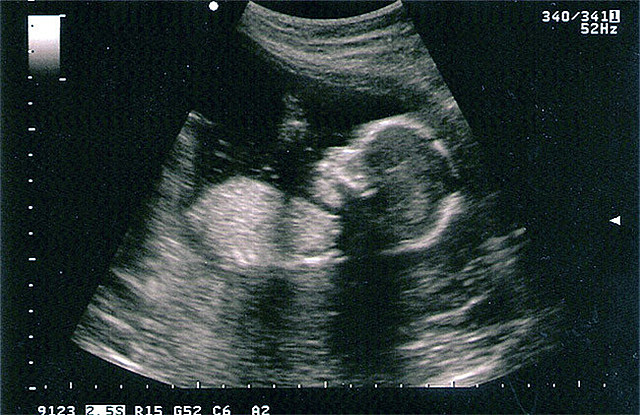

Se escucha el latido del corazón en las ecografías.

SEMANA 9: Movimientos involuntarios

Formación de: órganos sexuales, parpados, oreja por dentro

SEMANA 10: De embrión a feto

corazón, cerebro, hígado, riñones e intestinos funcionando

Mejores articulaciones

La placenta funciona, saco vitelino se encoge

Traga líquido amniótico

SEMANA 11: Ya puede abrir y cerrar sus manos.

Se desarrolla el diafragma, hipo.

SEMANA 12: succiona

Riñones funcionan, orina

Conexiones neuronales en desarrollo para el funcionamiento del cerebro.